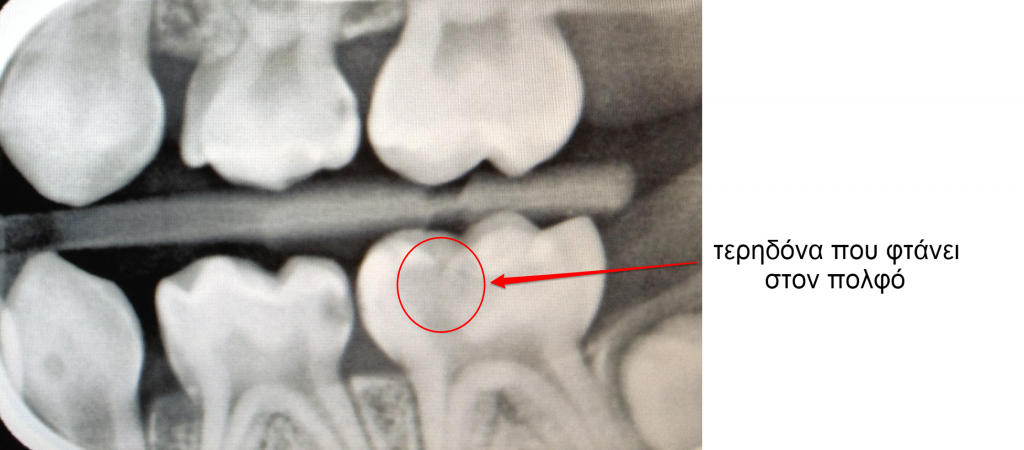

Όταν ένα παιδικό δόντι χαλάσει πολύ ή υποστεί κάταγμα και υπάρχουν σημεία και συμπτώματα όπως πόνος, φλεγμονή, νέκρωση του πολφού, απόστημα, συρίγγιο, τότε πρέπει να γίνει ενδοδοντική θεραπεία στο δόντι αυτό προκειμένου να γλιτώσει την εξαγωγή.

Η ενδοδοντική θεραπεία στα παιδικά δόντια μοιάζει με την ενδοδοντική θεραπεία που γίνεται στα μόνιμα δόντια αλλά δεν είναι ακριβώς η ίδια διαδικασία. Μετά το τέλος της, ανάλογα με το πόσο αδυνατισμένο είναι το δόντι από την καταστροφή που υπέστη, μπορεί να του τοποθετήσει ο παιδοδοντίατρος στεφάνη για να το προστατέψει.